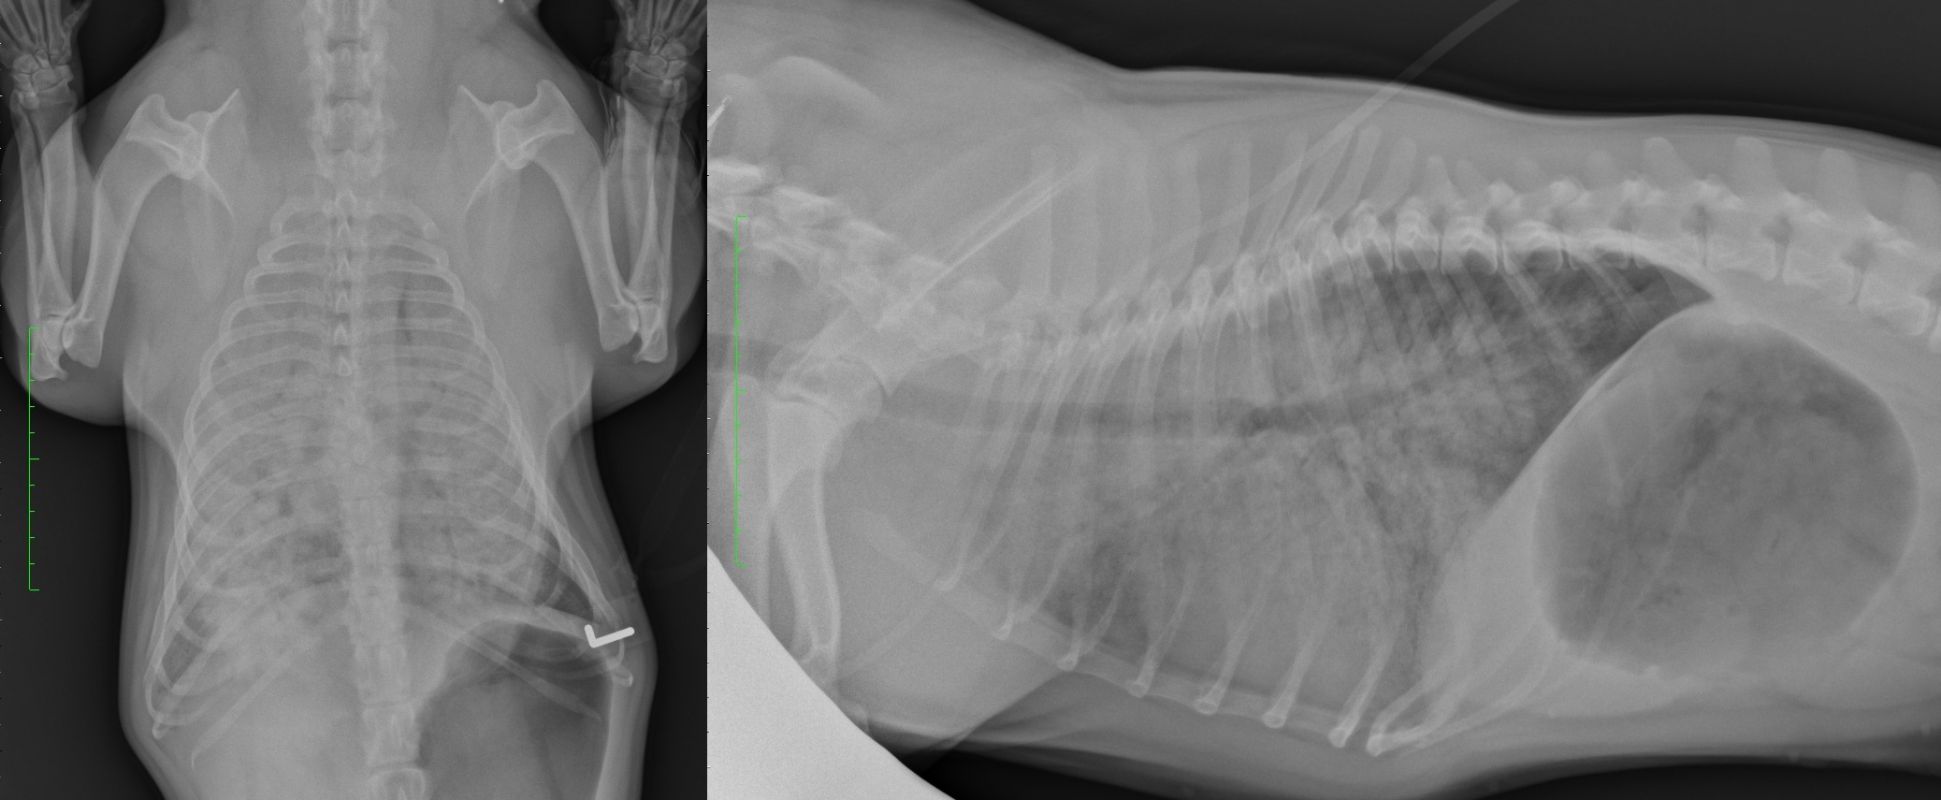

OEdème aigu pulmonaire cardiogénique du chien décision d'hospitalisation, organisation et. Découvrez des conseils pratiques pour traiter l'œdème pulmonaire chez votre chien Qu'en est -il chez nos petits compagnons chiens et chats ? comment se traduit un œdème pulmonaire ? Quelles sont les causes qui peuvent y conduire ? Comment soigner un œdème pulmonaire chez un chien ou un chat ?